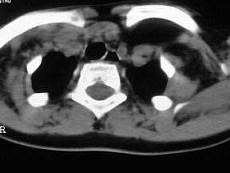

问题 女,17岁,发现左侧颈部包块半年余,PE:病灶质软,境界不清,无压痛,CT如图所示,应诊断为 ( )

选项 A、颈部淋巴管瘤 B、颈部陈旧性血肿 C、颈部畸胎瘤 D、颈部错构瘤 E、颈部脂肪瘤

答案 E